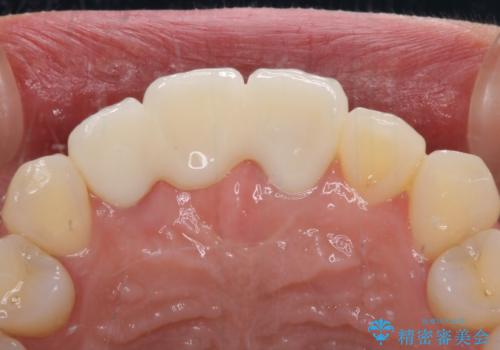

治療途中で放置した前歯 オールセラミックブリッジ

- 仮歯のまま前歯を放置しているとのことで来院された患者様です。

目視で確認できるほどしっかりとした破折が認められ、抜歯が必要と判断されました。

抜歯後は歯肉が痩せてしまうため、歯肉移植を行って歯肉の形態を改善した後、オールセラミックブリッジにて補綴することとしました。

歯肉移植により歯肉ラインや歯の形態を整えることができ、ブリッジによる補綴としたことで舞えば全体の色調を整えることができました。